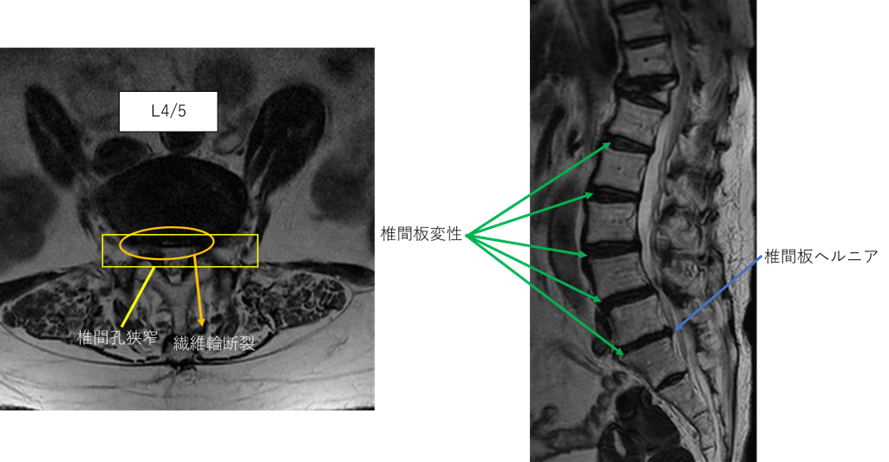

L1/2: 椎間板変性症

L2/3: 椎間板変性症

L3/4: 椎間板変性症

L4/5: 椎間板変性症、繊維輪断裂、両椎間孔狭窄

L5/S: 椎間板変性症、椎間板ヘルニア、繊維輪断裂

以上の事が画像上認められます。

L4/5、5/s に

椎間板変性症、繊維輪断裂、椎間孔狭窄、椎間板ヘルニアを認め、主症状の原因の可能性が高い。